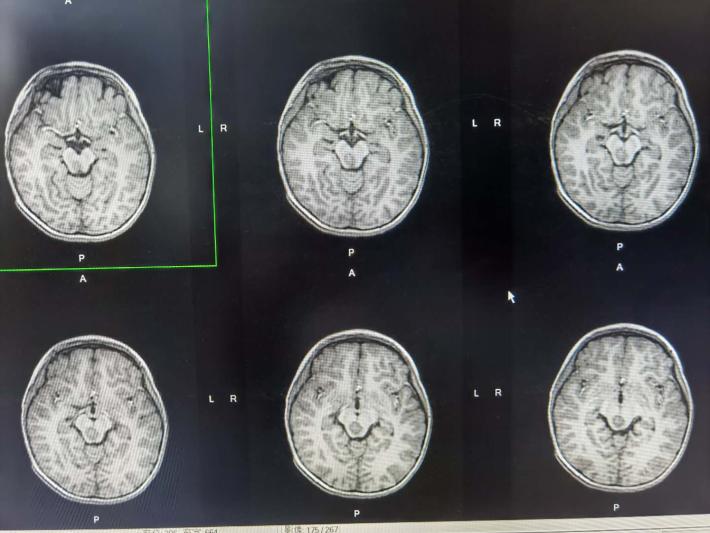

术前轴位

术前轴位,可见肿瘤,用来对比术后轴位